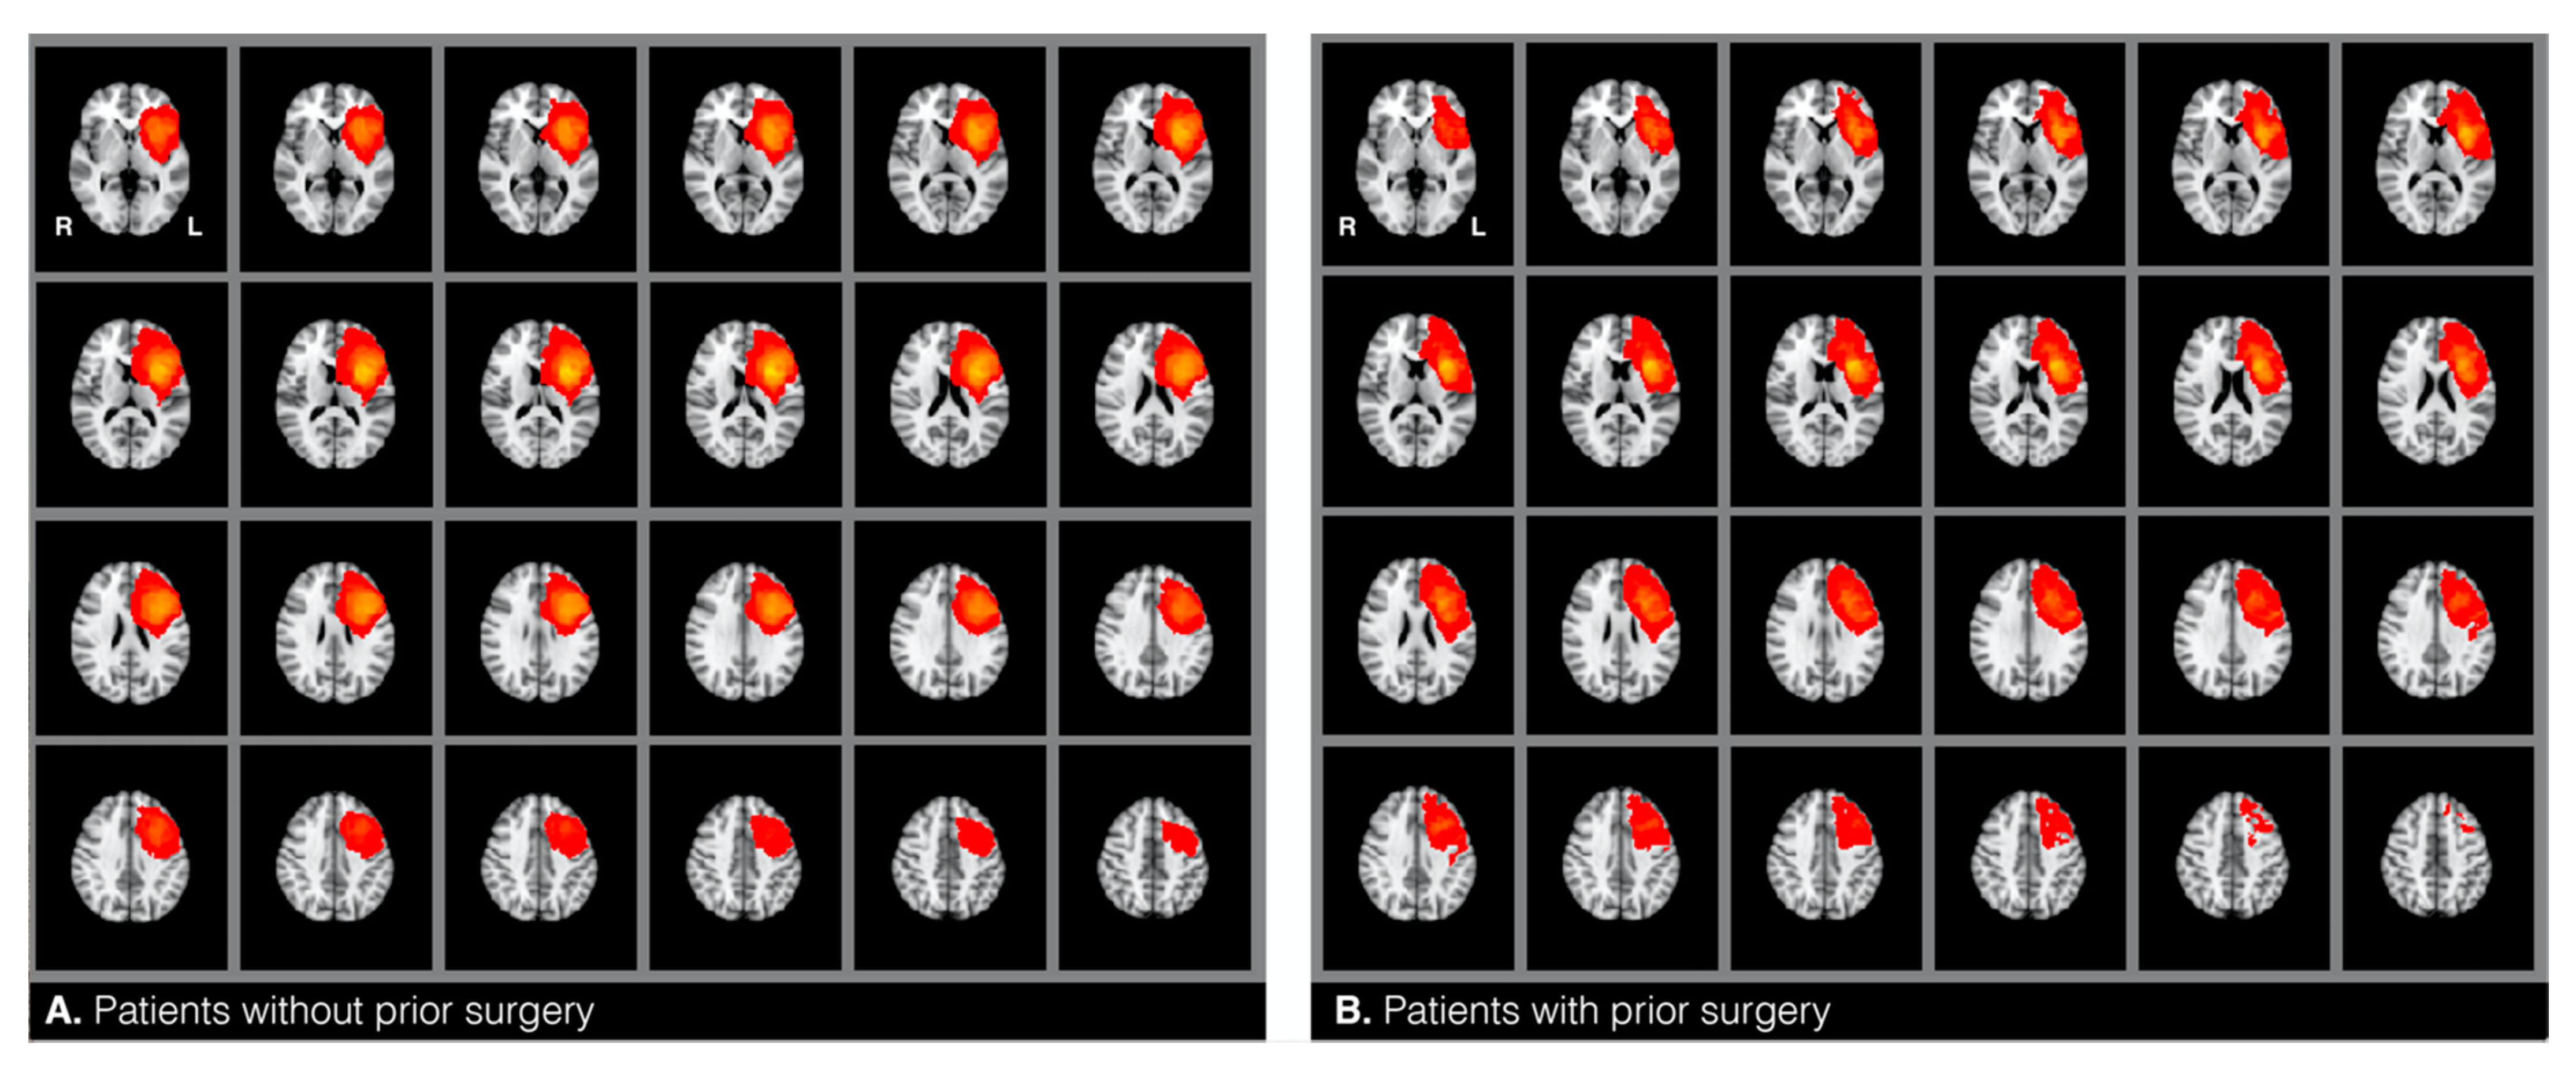

The target and the control groups were statistically compared based on twelve variables that can potentially confound fMRI language dominance [1,2,3,4,5,6,7]. These included: (1) glioma hemisphere, and (2) location—all patients included in this study had a brain tumor around the left inferior frontal gyrus (see heat maps in Figure 1), (3) glioma volume—mean tumor size was calculated for each group by drawing tumor masks (see below), (4) glioma grade—i.e., low versus high grade, with additional consideration of the frequency of distribution of grades I−IV, and (5) glioma type [17]. Glioma grade and type were determined through record review. All patients were diagnosed with type I tumors, which are diffuse astrocytic and oligodendroglial tumors (gliomas) [17]. We compared the frequency of the distribution of the following glioma types between the two samples: glioblastoma, anaplastic astrocytoma, oligoastrocytoma, and oligodendroglioma. We also compared the samples based on (6) the presence of aphasia and (7) the history of seizures. The two factors were accessed from information gathered during the patients’ fMRI visit and/or from record review indicating aphasia diagnosis by a neuropsychologist. Additionally, the samples were compared on the following demographic variables: (8) handedness, (9) age, and (10) gender. These were identified from patient reports and record reviews. To assess handedness, patients were asked to indicate with which hand they wrote. This information was checked against record reviews for concordance. Finally, we also reviewed how many patients underwent (11) chemotherapy and (12) radiotherapy across the two groups. Chi-square and Fisher’s exact tests were used to analyze categorical variables when appropriate. An independent samples t-test was used to analyze continuous mean age differences. The Mann–Whitney-U test was used to compare glioma volumes between the two samples.

Figure 1.

Heatmaps representing the location of gliomas in patients without (A) and with (B) prior surgery.

2.4.2. Glioma Identification

Individual glioma borders were based on the changes in signal intensity on T2. With the T2 boundaries, we manually drew masks around the patients’ glioma on T2-weighted MRI scans in FMRIB Software Library View (FSLView) and additionally used T1 images for reference. A second (senior) investigator reviewed each of the masks for accuracy. The tumor masks included the center of the glioma, dense surrounding edema (if any), and any previous resection cavity, as all of these lesion characteristics can distort language signals. T2 images were skull-stripped using a “bet” command. Using linear regression (12 degrees of freedom), the betted images were transformed to normalized brain space (Montreal Neurological Institute, MNI, 152 T-1 weighted, 2 mm). A “flirt” command was applied to transform tumor masks from individual space to the MNI space. Next, an “fslstats” command was used to calculate tumor volume of the transformed tumor masks. We reviewed the distribution of the glioma masks by overlaying all the masks within each of the two samples and thereby generated heat maps for each of the two groups in the MNI space (Figure 1). Finally, also using the MNI space, we calculated glioma volume using the tumor masks (fslstats).